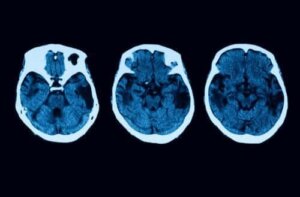

Diagnostiske tests slutter dog ikke der. For at være helt sikker, vil der blive udført andre neurologiske tests, såsom MR og tomografier. Hvis alt tyder på, at du muligvis har posterior kortikal atrofi, er der forskellige behandlinger, du kan vælge.